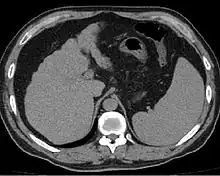

![]() | |

| Cross-section of human liver with cirrhosis | |